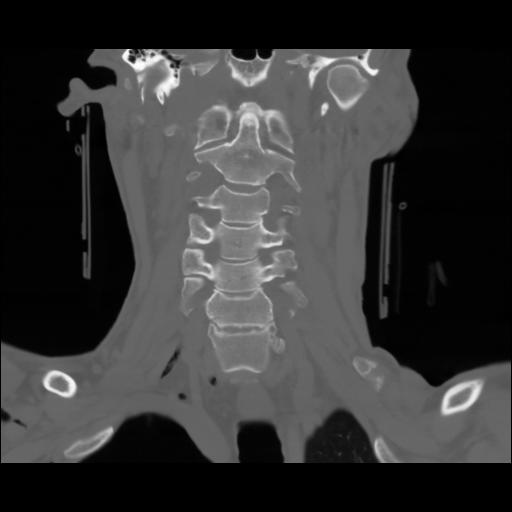

13 P.BLANDAS,,Coronal,2.000,P.BLANDAS,Coronal,